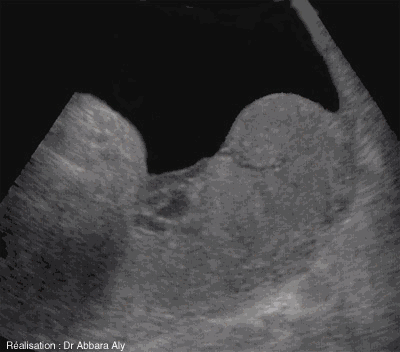

Coupe échographique sur le placenta

à 38 semaines d'aménorrhée